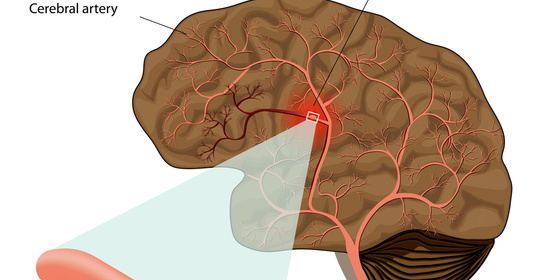

血管收縮性頭痛:治療與管理

全頭痛:原因多樣,治療各異,及時就醫

情緒性頭痛:緩解方法與建議